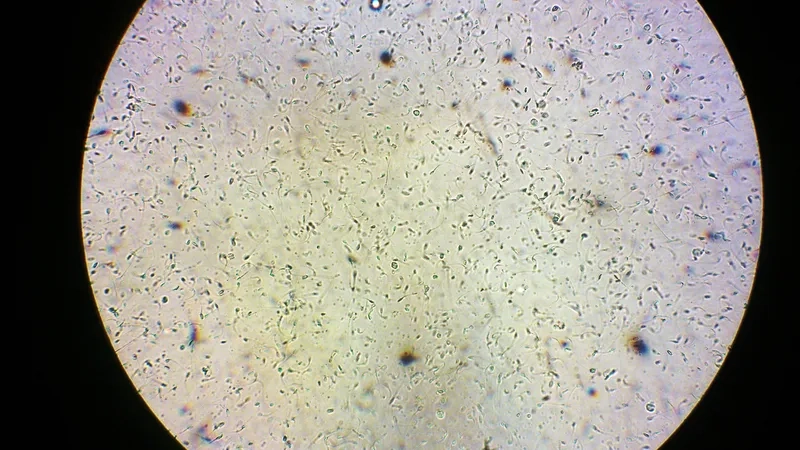

Tinh trùng dưới kính hiển vi là một cảnh tượng sinh học kỳ thú, đồng thời là hình ảnh cốt lõi trong xét nghiệm tinh trùng (tinh dịch đồ). Việc kiểm tra tinh trùng giúp đánh giá khả năng sinh sản của nam giới.

Khám phá những hình ảnh tinh trùng dưới kính hiển vi trong bộ sưu tập này sẽ cho thấy sự khác biệt rõ rệt giữa hình thái tinh trùng bình thường với tinh trùng dị dạng.